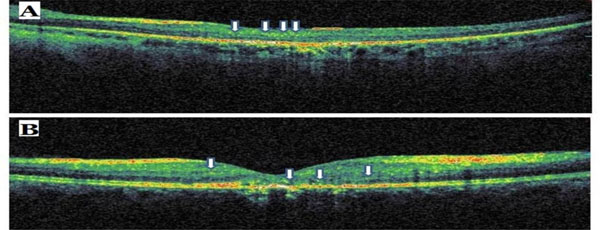

Sample optical coherence tomography scans from patients with commotio retina (A) and central retinal artery occlusion (B). The arrows indicate hyperreflective dots.